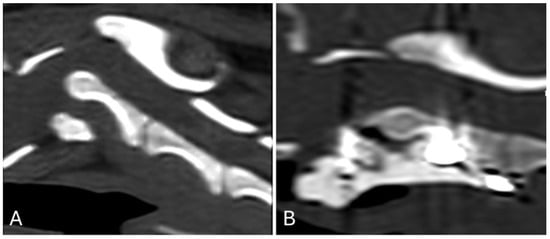

Post-operative images showed correct implant positioning and normal location of the dens within the respective fovea along the ventral arch of C1 (Figure 3 and Figure 4).

Figure 3. Lateral view of the cervical spine before (A) and after (B) surgical treatment. Correct screw insertion can also be observed.